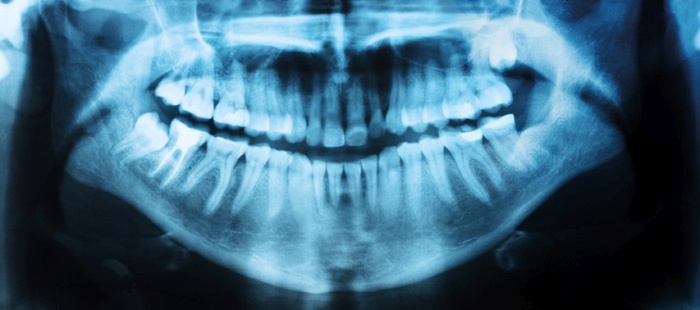

Rentgenska slika celotnega zobovja (ortopan). Rentgensko slikanje zgolj za potrebe ocenjevanja starosti prosilcev za azil je v Sloveniji obvezno, kljub negativnim stranskim učinkom.

Ko smo ob začetku delovanja novega sistema (po katerem je rentgen, ki ima močne negativne stranske učinke, obvezen) etične dileme naslovili na pristojne v zdravniškem društvu, smo dobili nedvoumne odgovore. V njihovem imenu sta spregovorila dr. Katarina Šurlan Popovič, predstojnica katedre za radiologijo na ljubljanski medicinski fakulteti, in Dean Pekarovič z inštituta za radiologijo. Pojasnila sta, da »sevalna zakonodaja temelji na zahtevi, da mora biti vedno za izpostavljanje sevanju znan upravičen razlog. Zato se tu postavlja etično vprašanje, ki pa ni z medicinskega področja, temveč seže na področje politike. Za nezdravstvene razloge izpostaviti osebo sevanju po mnenju stroke ni opravičljivo.« O smiselnosti zobnega rentgena za ocenjevanje starosti prosilcev za azil je spregovorila tudi dr. Nataša Ihan s katedre za maksilofacialno kirurgijo: »Modrostniki normalno izraščajo med 18. in 30. letom, podočniki in ličniki med 13. in 14. letom. Torej ortopan pri mejno starih najstnikih ni natančen, saj njihove starosti ne napove. Možna starost osebe je torej med 14 in 30 let.«